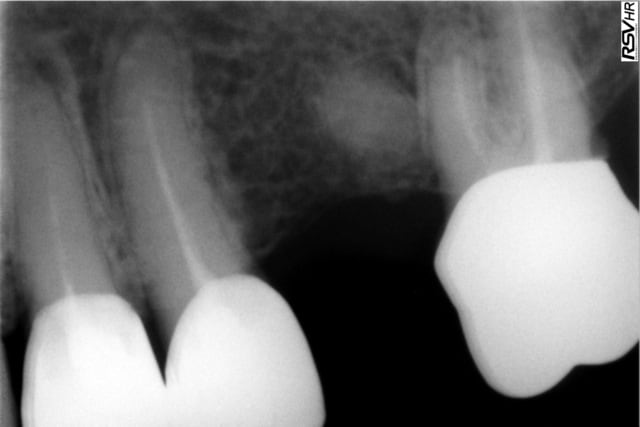

j'avais donc plutôt bon espoir mais les douleurs au niveau de cette 24 sont encore presentes avec une legere voussure au niveau du vestibule, moins fortes mais toujours présentes.(radio ci jointe)

question:puis je encore espere une guerison et attendre encore ou dois je re-reprendre le traitement parceque sur la derniere radio les images apicales n'ont pas vraiment disparues????